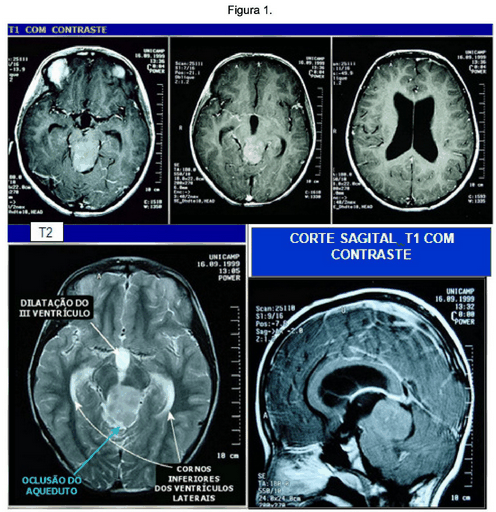

Paciente Feminina de 9 anos. Desde os 5 anos tem epilepsia e diagnóstico de tumor cerebral. Feita biópsia, material inconclusivo. Sete meses após a cirurgia continuava com piora progressiva da cefaléia e crises epilépticas esporádicas. Atualmente apresenta déficit cognitivo e hipoacusia E. As imagens da ressonância magnética e o laudo estão apresentados nas Figuras 1 e 2, e no Texto 1, respectivamente.

Ressonância Magnética de Crânio. Cortes Axiais T1 com contraste e T2; Corte Sagital com contrate.

Fonte: UNICAMP. Anatomopatológico.

O Laudo da Ressonância Magnética: Os cortes axiais mostram lesão bem delimitada e aproximadamente esférica no mesencéfalo, ocupando quase todo o tegmento e a placa quadrigêmea, com obliteração do aqueduto de Sylvius e hidrocefalia supratentorial (afetando o III ventrículo e os laterais). A lesão tem aspecto expansivo e comprime o vermis superior.

Nos cortes pesados em T2 a lesão mostra-se predominantemente homogênea e com hipersinal, indicando tratar-se de uma lesão hidratada. Não há componente cístico. Os cortes sagitais, T1 com contraste mostram Tumor Sólido, bem delimitado, originado na placa quadrigêmea; comprime anteriormente o mesencéfalo e posteriormente a porção anterior do vermis. Impregna-se de forma difusa e levemente heterogênea. O halo de liquor em volta da lesão na cisterna cerebelar superior demonstra que o tumor provém do mesencéfalo. Os cortes coronais T1 em contraste mostram que o tumor é originado na placa quadrigêmea deforma o III ventrículo (Situa-se no nível da incisura do tentório e eleva a pineal, mas não a invade).